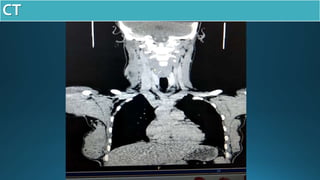

CT NECK

cystic mass with

internal sepation

enhancement of cystic wall

internal jugular common

carotid

sternocleodomastoid

carotid bifurcation

ramus of right mandible

axilla

lymph nodes